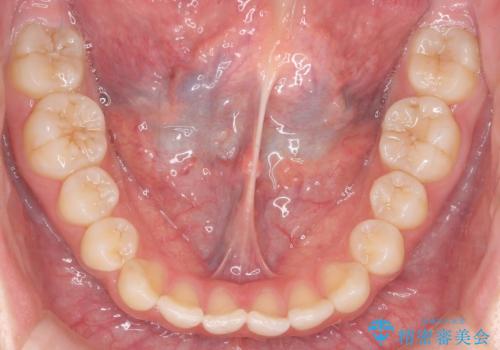

咬んでも向こう側が見える、前歯が閉じない症状でした。また、上の前歯が少し前に出ている状態でした。

上の前歯をわずかに削る処置を行い、後ろに下げながら下の歯となるべく咬むように矯正治療を行いました。